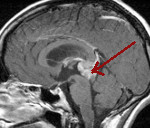

• Нейровизуализацию. Предпочтение отдаётся МРТ головного мозга, в старшем возрасте при наличии противопоказаний к МРТ возможно проведение церебральной КТ. Нейровизуализирующие методики дают возможность диагностировать неоплазию, определить характер её роста, установить локализацию и распространённость процесса.